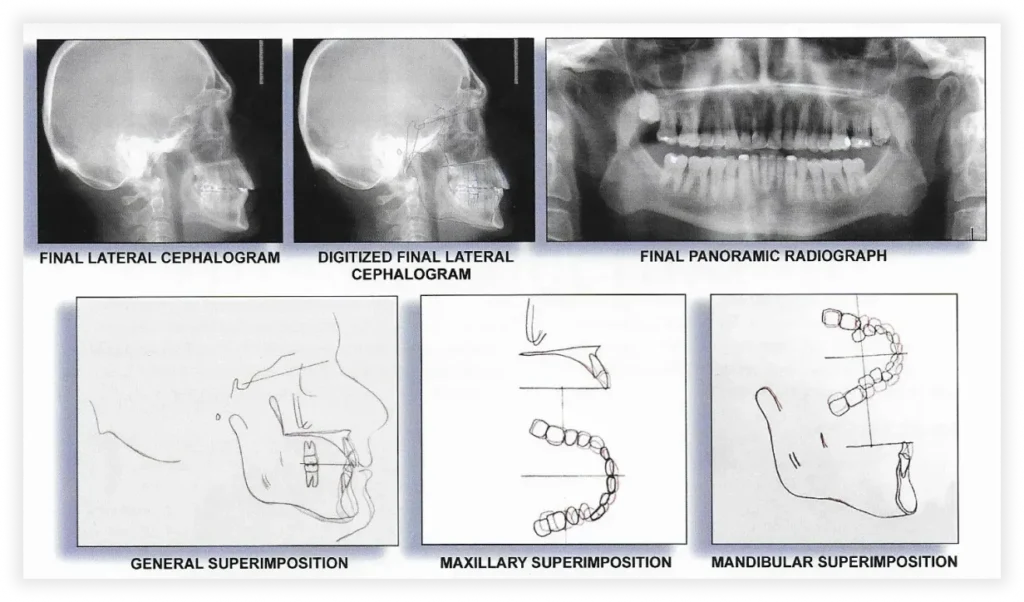

Final Photos